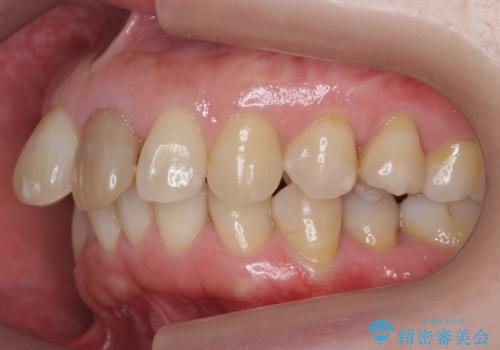

右上1はひっこめた量が大きかったため、反対側の1番と切端をそろえるのに、多少長さは長くなりました。

右上2、左上2の補綴も提案はしましたが、最小限の本数で行っていくことになり、右上2の捻転(歯のねじれ)はそのままとなっております。